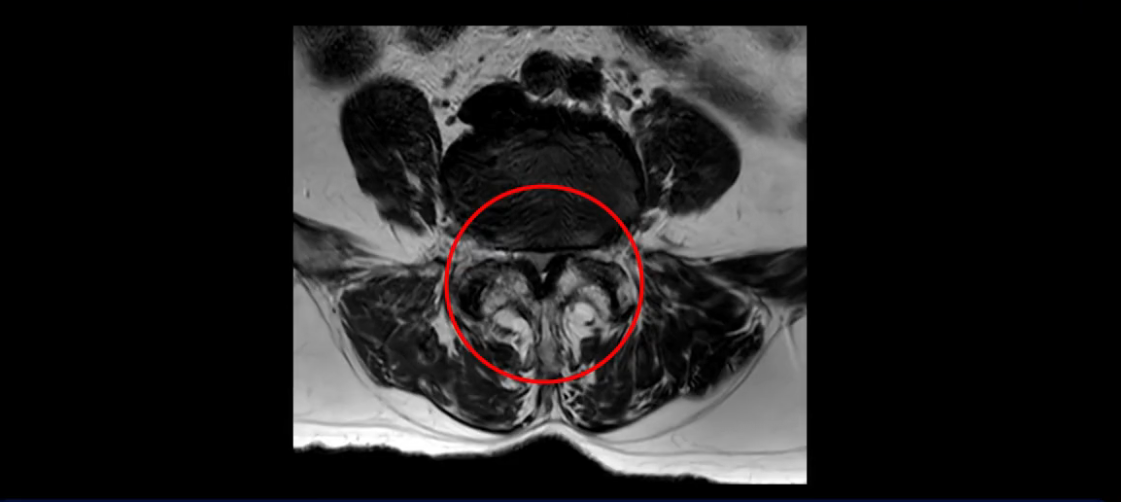

먼저 이분 MRI를 보고 자세히 설명해 드린 후 어떻게 허리 여러 마디에서 협착과 전방전위로 신경이 심하게 눌려 보이는 환자가 수술 없이 좋아질 수 있는지, 또 치료는 어떻게 하는지 설명해 드리겠습니다.

이분 MRI 보시면 허리 3마디의 퇴행이 매우 심합니다.

또 척추관협착도 매우 심합니다.

척추관이 심하게 좁아져 있습니다.

이렇게 여러 마디가 안 좋고 뼈도 밀려 나가 있으니까 나사박는 수술해야 하는데, 대학병원에서도 수술을 한 번에 못 하고 두 번에 나눠서 해야 한다고 들으셨습니다. 왼쪽으로 신경가지가 빠져나가는 추간공도 많이 좁아져 있습니다.

이렇게 신경 구멍들이 좁아져 있고 신경이 눌리니까 엉덩이와 다리가 너무 저리고 아파서 아예 일어서질 못하니까 휠체어를 타고 병원에 내원하셨는데요. 그럼 어떻게 이분처럼 신경이 눌려있는 환자분들을 수술 없이 치료해서 잘 걷게 만들고 엉덩이와 다리가 저리고 아픈 증상이 사라지게 할까요? 지금부터 설명해 드립니다.